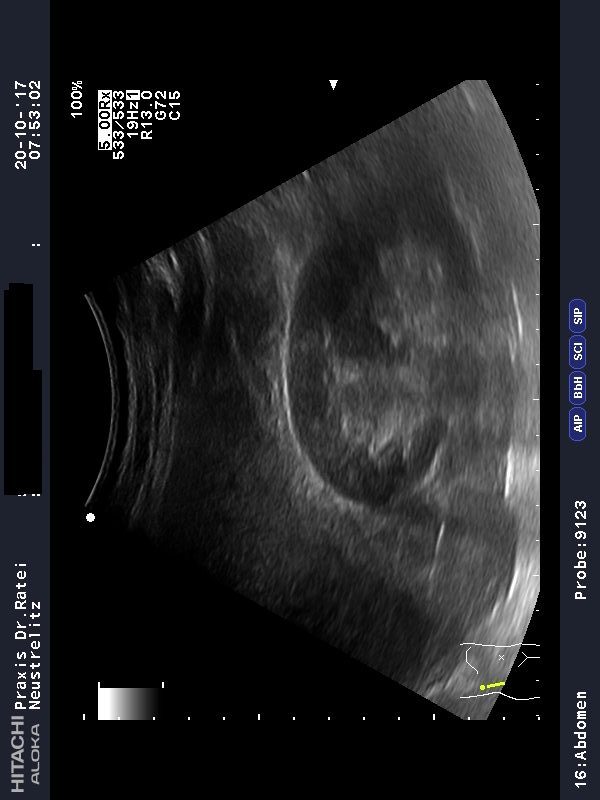

Niere